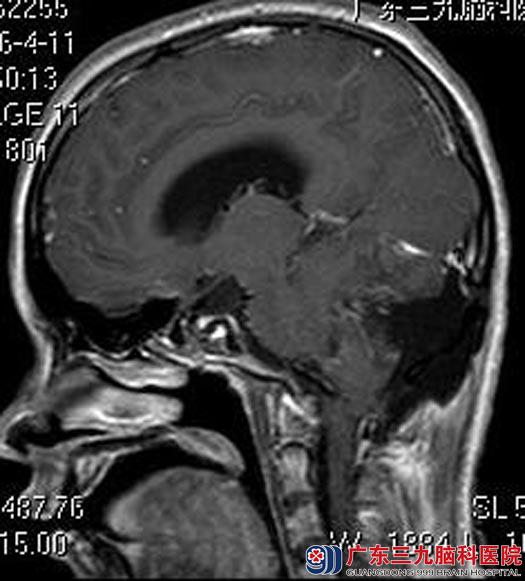

婷婷的父母立即带着她来到广东三九脑科医院,头颅MR检查提示:右侧小脑半球占位性病变,病灶大小约为6.6cm×5.8cm×5.1cm,增强后壁结节呈明显不均匀异常强化影,囊壁未见明显强化。四脑室受压变窄,脑干受压变形,小脑扁桃体变尖,向下疝入枕骨大孔,幕上脑室系统明显扩张,考虑毛细胞星形细胞瘤可能,待排血管母细胞瘤。

婷婷父母详细了解病情后要求手术治疗。由鲁明主任主刀,在全麻下行右侧小脑半球肿瘤切除术,术中显微镜下见灰褐色肿瘤组织,质软,边界较清,予显微镜下完整切除,手术顺利。术后婷婷很快清醒,未再出现呕吐症状,头晕症状也明显好转。术后病理提示:多形性黄色星形细胞瘤(WHO II级)。